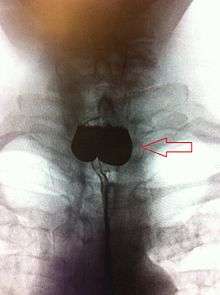

The simple barium swallow will normally reveal the diverticulum. It may also be found with upper GI endoscopy, or CT with oral contrast.

If small and asymptomatic, no treatment is necessary. Larger, symptomatic cases of Zenker's diverticulum have been traditionally treated by neck surgery to resect the diverticulum and incise the cricopharyngeus muscle. However, in recent times non-surgical endoscopic techniques have gained more importance (as they allow for much faster recovery), and the currently preferred treatment is endoscopic stapling[4][5] (i.e. diverticulotomy with staples ). This may be performed through a diverticuloscope. Other methods include fibreoptic diverticular repair.[6]